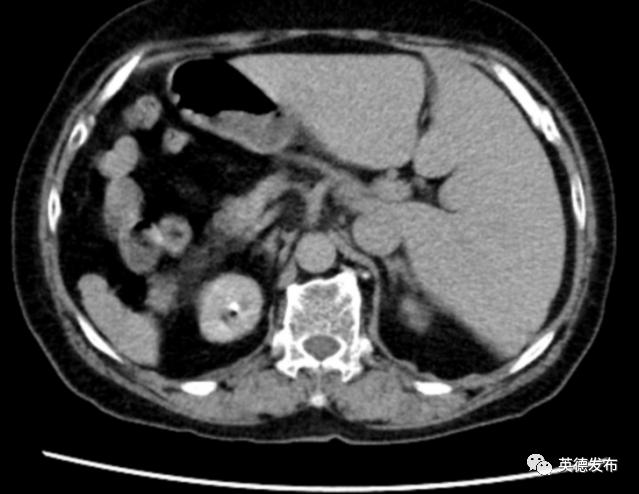

为进一步寻找“元凶”,医护团队充分做好相关应急预防措施,马上通过先进的80排160层螺旋CT,实施胸部血管螺旋CT血管成像(即“胸部血管CTA”),可见患者右肺上叶舌段动脉,左肺下叶动脉闭塞,余双肺各叶大部分闭塞,管腔明显狭窄,于是迅速作出诊断:大面积肺栓塞,已出现休克症状,患者随时可能死亡。